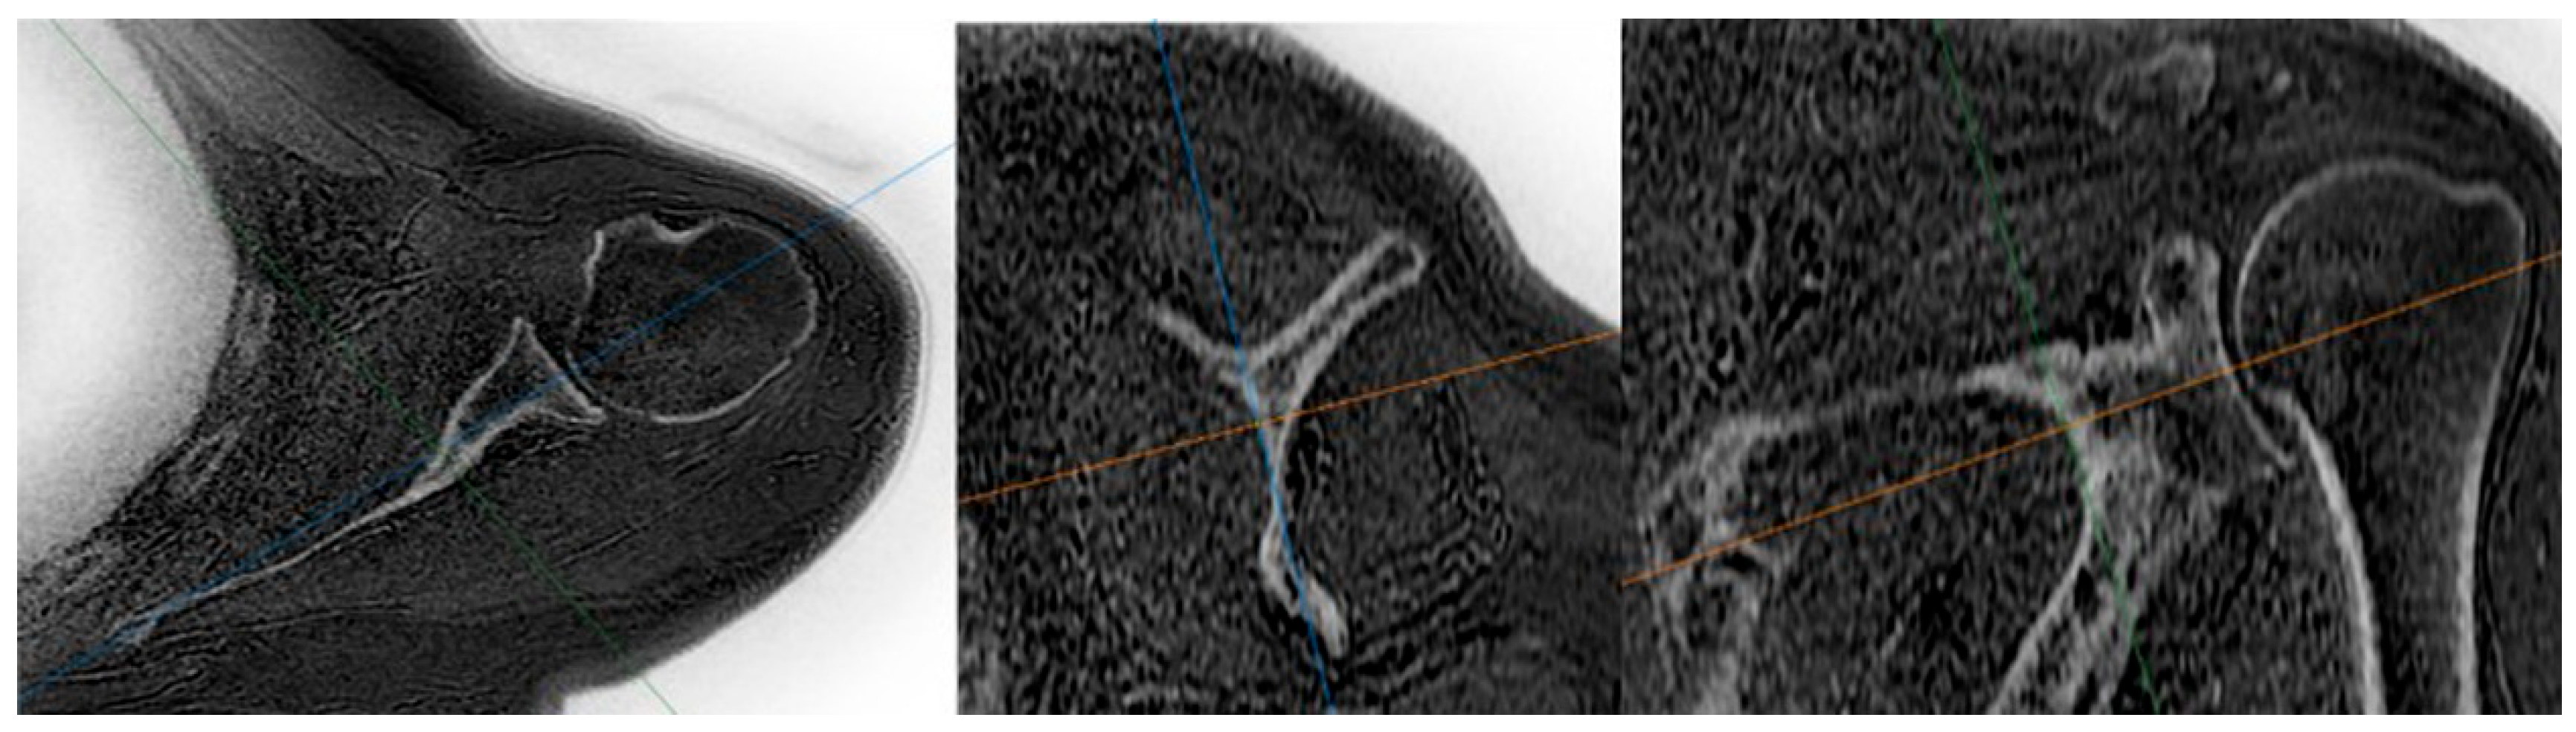

- MRI-based measurements